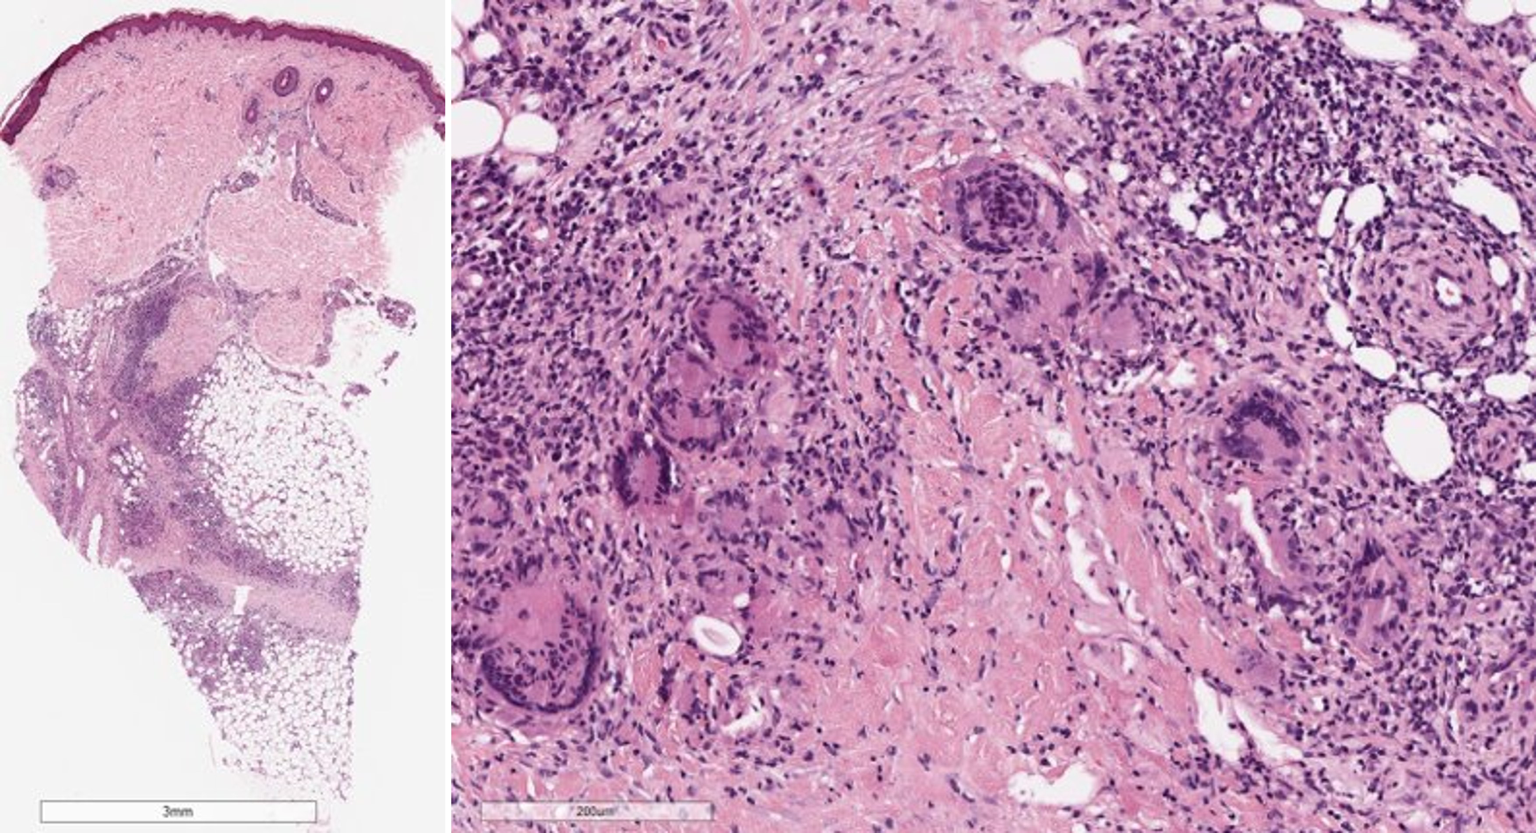

Abb. 2

Histologisches Bild eines Erythema nodosum mit septaler Pannikulitis (Hämatoxylin-Eosin-Färbung): Das entzündliche Infiltrat ist vorwiegend auf die verdickten und fibrotischen Septen der Subkutis beschränkt. Das entzündliche Infiltrat ist überwiegend lymphozytär mit einer Beimischung von eosinophilen Granulozyten, Plasmazellen und vielen vielkernigen Riesenzellen. Die Gefäße sind unauffällig

Histopathologie

Die Histologie wird charakterisiert durch eine septale Pannikulitis ohne begleitende Vaskulitis. Die Zusammensetzung des entzündlichen Infiltrates ändert sich im Verlauf: Im Initialstadium zeigt sich im Korium ein schütteres perivaskuläres lymphozytäres Infiltrat, im Bereich des Fettgewebes zeigen sich septal und paraseptal Infiltrate neutrophiler Granulozyten mit einer Verbreiterung der subkutanen Septen durch das Ödem. Das Vollbild ist gekennzeichnet durch perivaskuläre und im Fettgewebe überwiegend septale histiozytenreiche Infiltrate mit Beimengung von Riesenzellen und neutrophilen Granulozyten. In der Subkutis finden sich durch fibrotischen Umbau verdickte Septen. Charakteristisch sind die sog. Miescher-Radiärknötchen, hierbei handelt es sich um paraseptale Granulome mit mehrkernigen histiozytären Riesenzellen (Abb. 2; [26]).